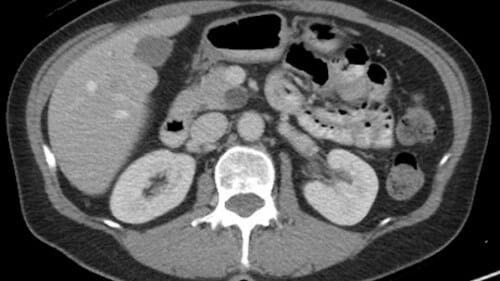

Harnessing machine learning to improve medical imaging

A group of researchers from the College of Engineering, School of Medicine and Public Health and Department of Computer Sciences are developing algorithms and data processing methods to improve medical imaging techniques like CT scans and MRIs. The collaboration, called Machine Learning for Medical Imaging, began in 2018 and has already produced a new way to predict severe asthma progression based on CT scans of lungs. Ongoing projects are aimed at using machine learning to better diagnose aggressive kidney cancer and to predict whether pancreatic cysts have the potential to develop into malignant tumors via CT scan images.